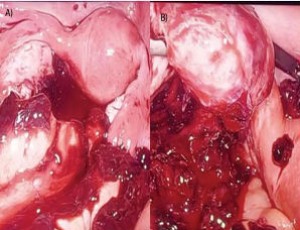

November 20, 2025 Case Report

Abstract Background: Ovarian ectopic pregnancy is a rare form of extrauterine gestation, accounting for less than 3% of all ectopic pregnancies. Its occurrence in the context of a unicornuate uterus and absent fallopian tube is exceedingly uncommon and pre..... -